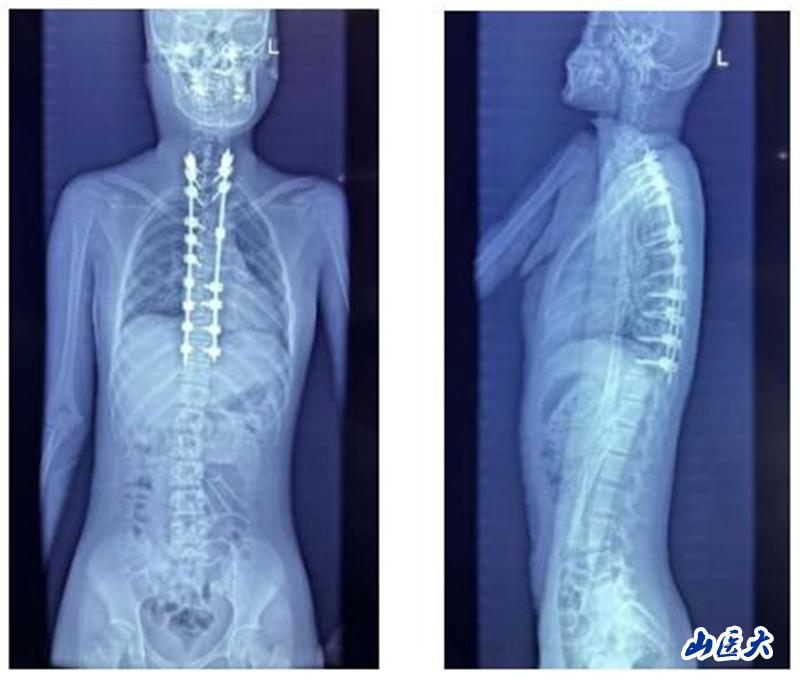

面對如此復雜病情,薛旭紅教授與趙勝教授帶領團隊精心策劃,為患者量身定制了個性化的手術方案。2024年12月27日,在主治醫師董政權、麻醉醫師、器械護士王淑珍和巡回護士杜娟的通力協作下,骨科團隊成功完成了這場高難度、高風險的手術。

術后,患者恢復情況良好,身體逐漸康復。考慮到患者家庭經濟困難,薛旭紅教授主動幫助患者聯系并申請北京海鷹脊柱健康公益基金會的救助。經過基金會評估,患者成功獲得全額費用資助,實現了免費治療。在醫護團隊和基金會的共同幫助下,小姑娘不僅免除了癱瘓的風險,更重新挺直了腰桿。